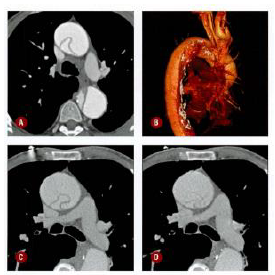

Homem de 57 anos, hipertenso e usuário de

cocaína, procura pronto atendimento por dor

torácica há 3 dias, de forte intensidade. Ao

analisar a tomografia de tórax com contraste,

realizada na admissão, é correto afirmar que